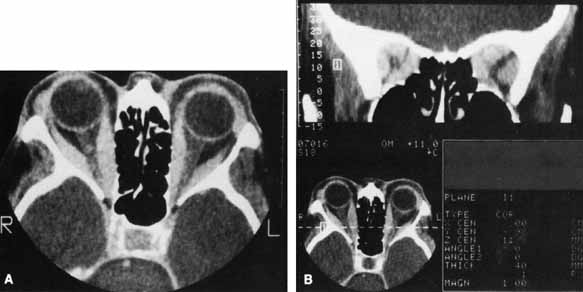

CT is not necessary in most patients who present with a clinical picture and supporting laboratory evidence of Graves' disease. It is, however, indicated when optic neuropathy is suspected, before orbital decompression, to examine the anatomic relationship of the orbit to both the sinus cavities and the cribriform plate, in patients with atypical proptosis or motility disturbances; or instead of ultrasonography to detect early thyroid orbitopathy in patients with equivocal results of laboratory tests. Like ultrasonography, CT allows reliable identification of even minimal enlargement of the recti muscles.40 Of those patients with clinical unilateral thyroid orbitopathy, CT will detect subclinical enlargement of the extraocular muscles on the contralateral side in 50%.75

The most characteristic CT finding in thyroid orbitopathy is enlargement of the extraocular muscles, which is usually bilateral and symmetric and has a fusiform configuration, with sharply defined borders and sparing of the tendinous insertions. Atypical cases with tendon involvement and blurred muscle margins have been described.75

The pattern of muscle enlargement on CT parallels that seen clinically. The inferior rectus is the most commonly involved, followed by the medial rectus, superior rectus, and lateral rectus. Other findings include proptosis and anterior prolapse of the orbital septum due to excessive orbital fat and muscle swelling (see Fig. 4).76 Also, lacrimal gland enlargement and bone remodeling without erosion can occur.75 Patients at risk for developing optic neuropathy may also have severe apical crowding, a dilated superior ophthalmic vein, and anterior displacement of the lacrimal gland.68 Of these, apical crowding is the most sensitive indicator for the presence of optic neuropathy (Fig. 5A).56 Both axial and coronal CT cuts should be obtained; the coronal plane is needed to assess the enlargement of the extraocular muscles at the apex (see Fig. 5B).